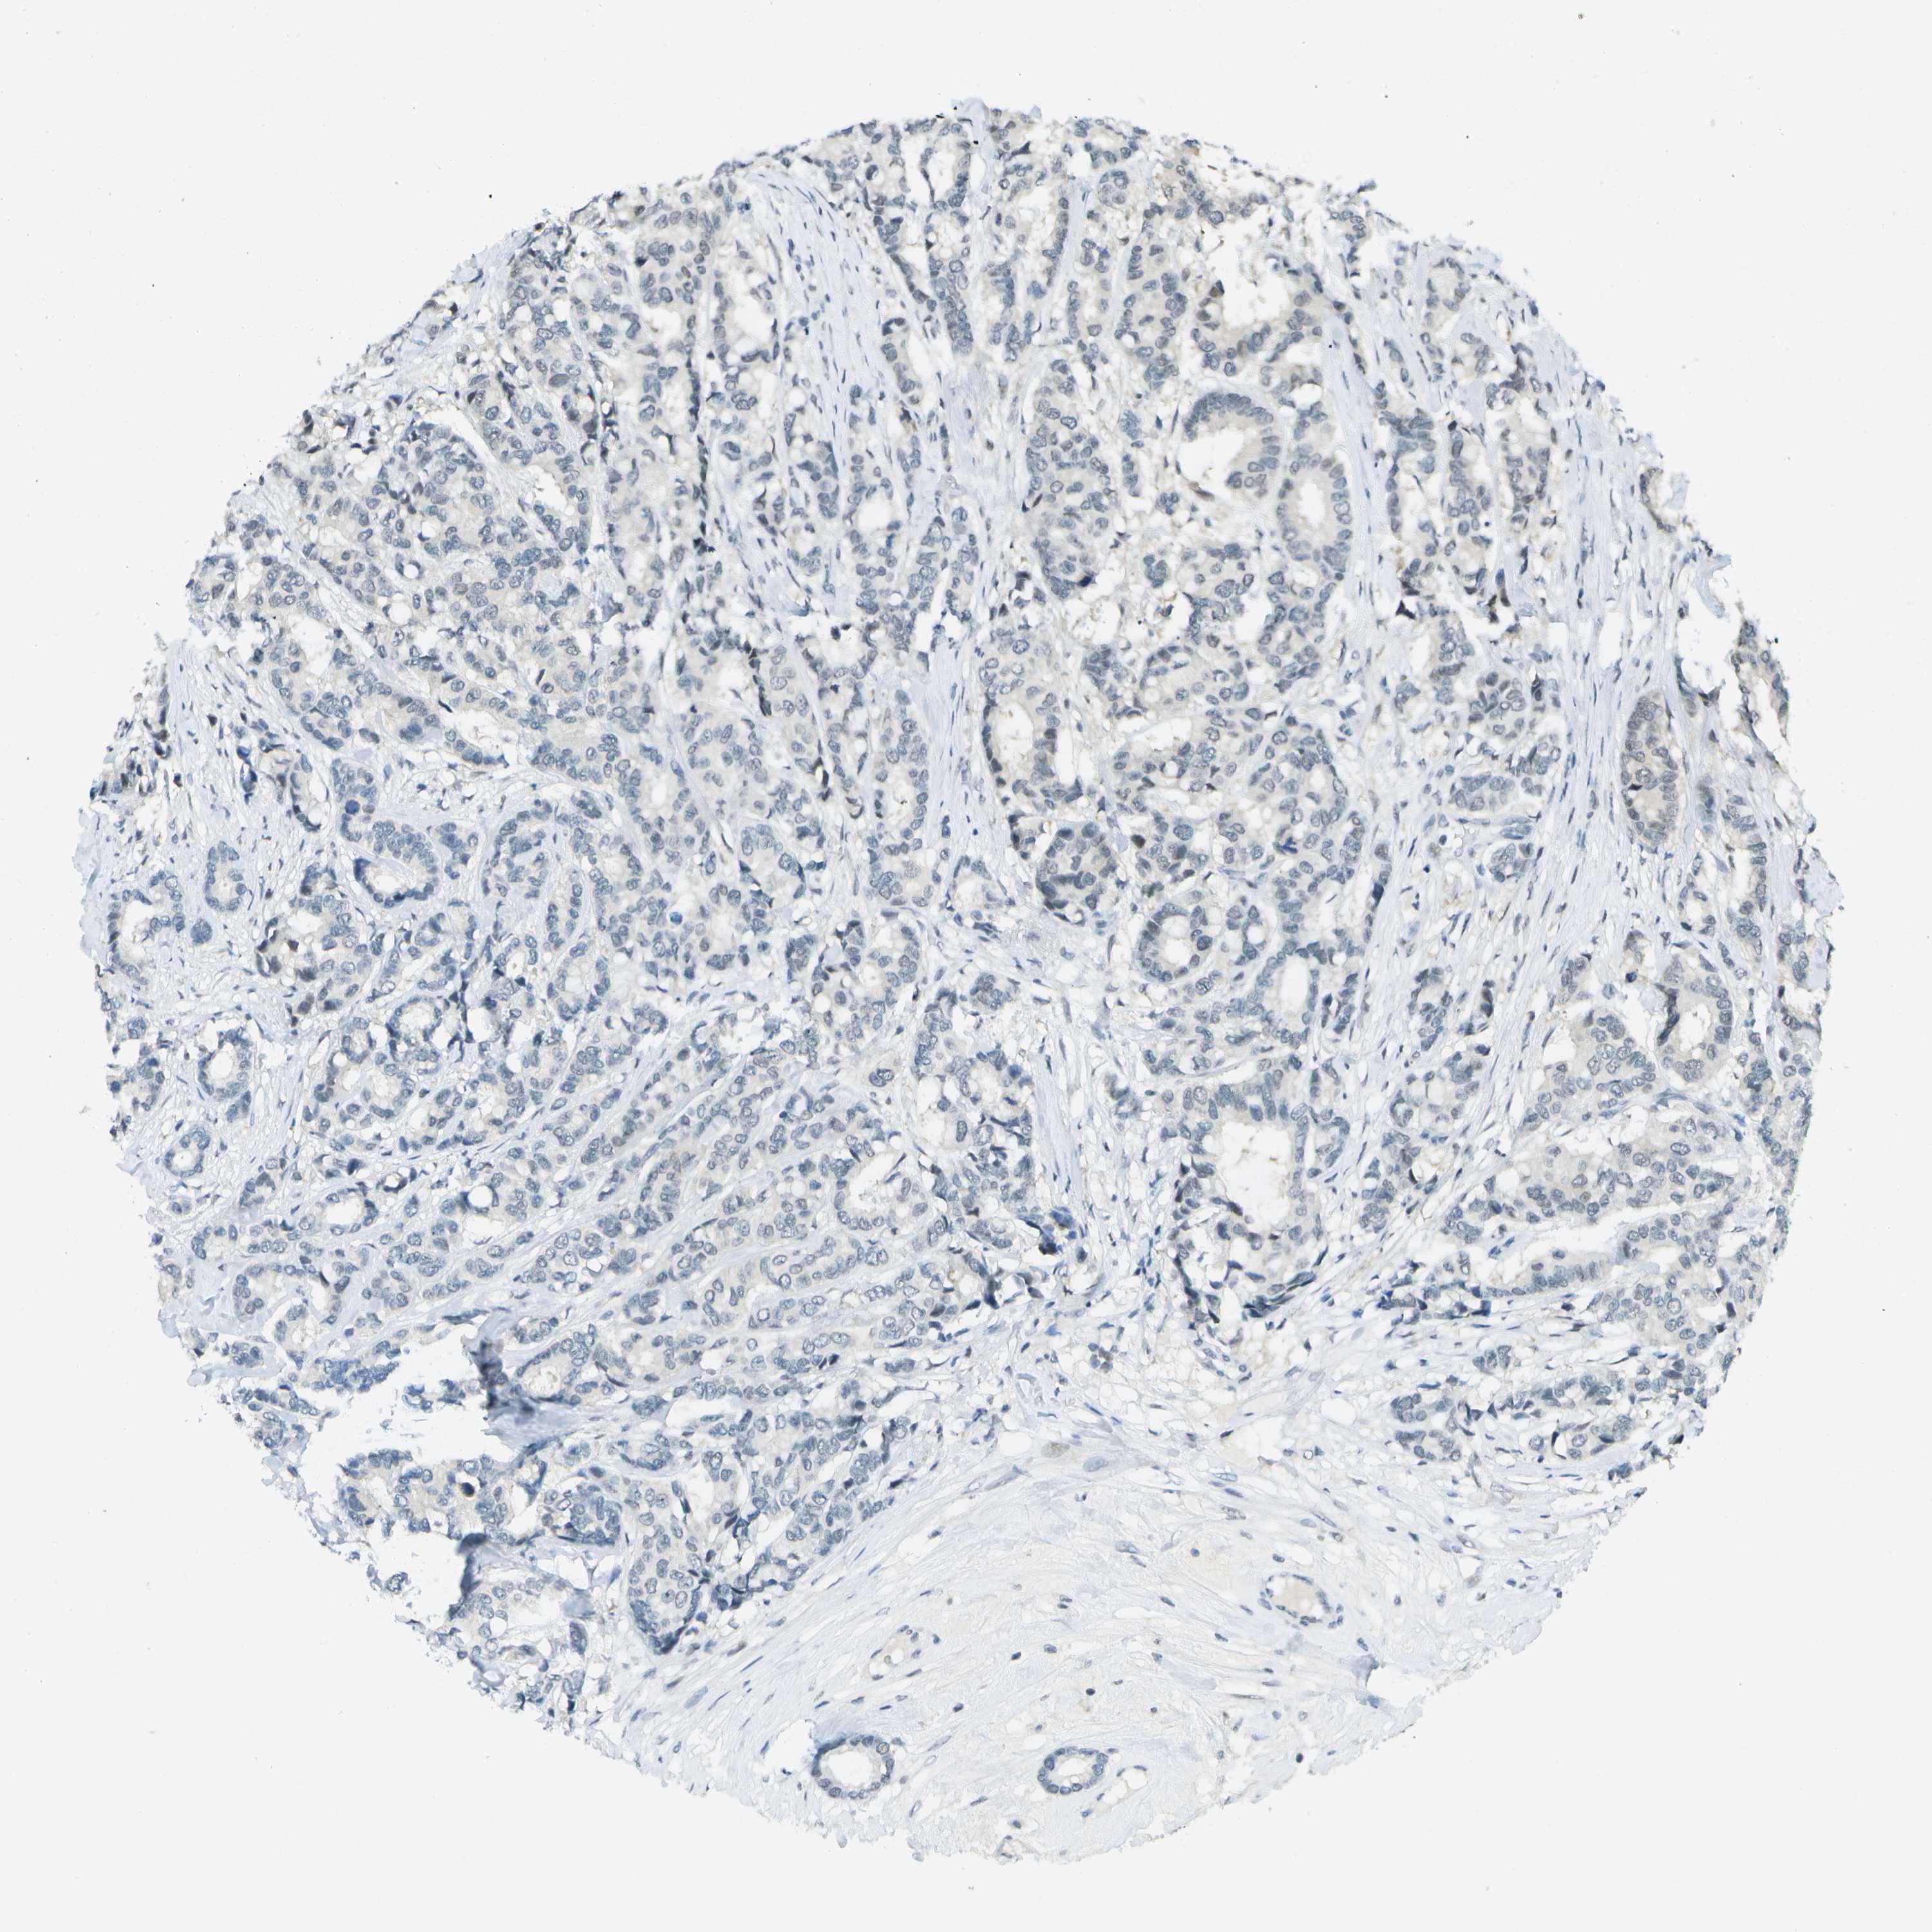

CANCER BREAST CANCER Show tissue menu

BRCA TCGA BRCA VALIDATION PROTEIN EXPRESSION

Breast cancer

Human cancer

Breast invasive carcinoma